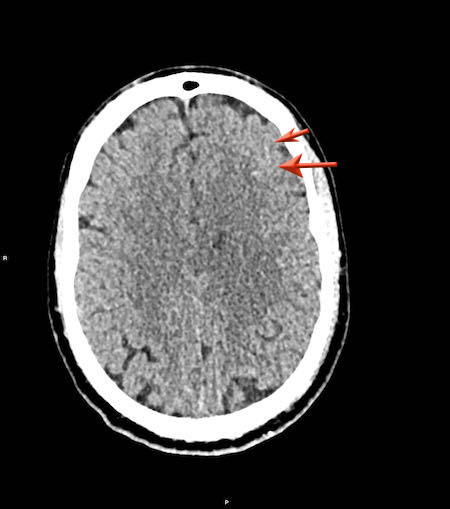

Đây là trường hợp tụ máu dưới màng cứng đồng tỷ trọng rất khó phát hiện (các mũi tên).

Lưu ý rằng ở mức cắt cao hơn có tụ máu dưới màng cứng hai bên.